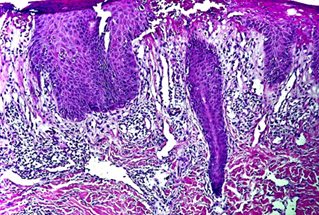

Figure 2.

Infiltrate that extends from the papillary dermis to the reticular dermis in

smaller extent, composed mainly by lymphocytes, histiocytes some neutrophilus

and accompanyed by einophilus, and a smaller number of large atypical

lymphates.

Courtesy Dra.

Johanna Brito - LunaPiel